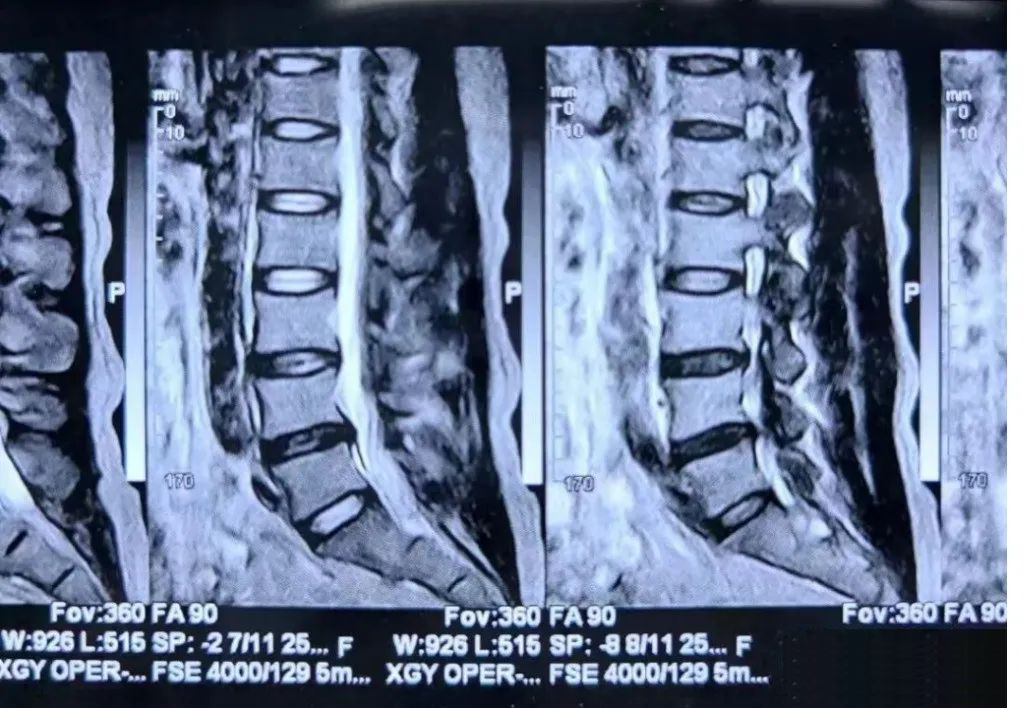

患者青年男性,以腰部疼痛为主诉入院。患者诉腰部疼痛,久坐及长时间行走时疼痛明显,平卧时疼痛减轻,夜间加重。患者腰椎CT未见明显腰椎间盘突出,但腰椎磁共振示L4-5椎间盘退变明显,诊断椎间盘源性腰痛。保守治疗只能缓解部分疼痛症状,不能解除引起腰痛的直接原因,可以进一步行腰椎间盘射频消融术治疗。

上图:腰椎磁共振示L4-5椎间盘突出不明显,但退变明显,行C臂X线引导下L4-5椎间盘双侧射频消融术